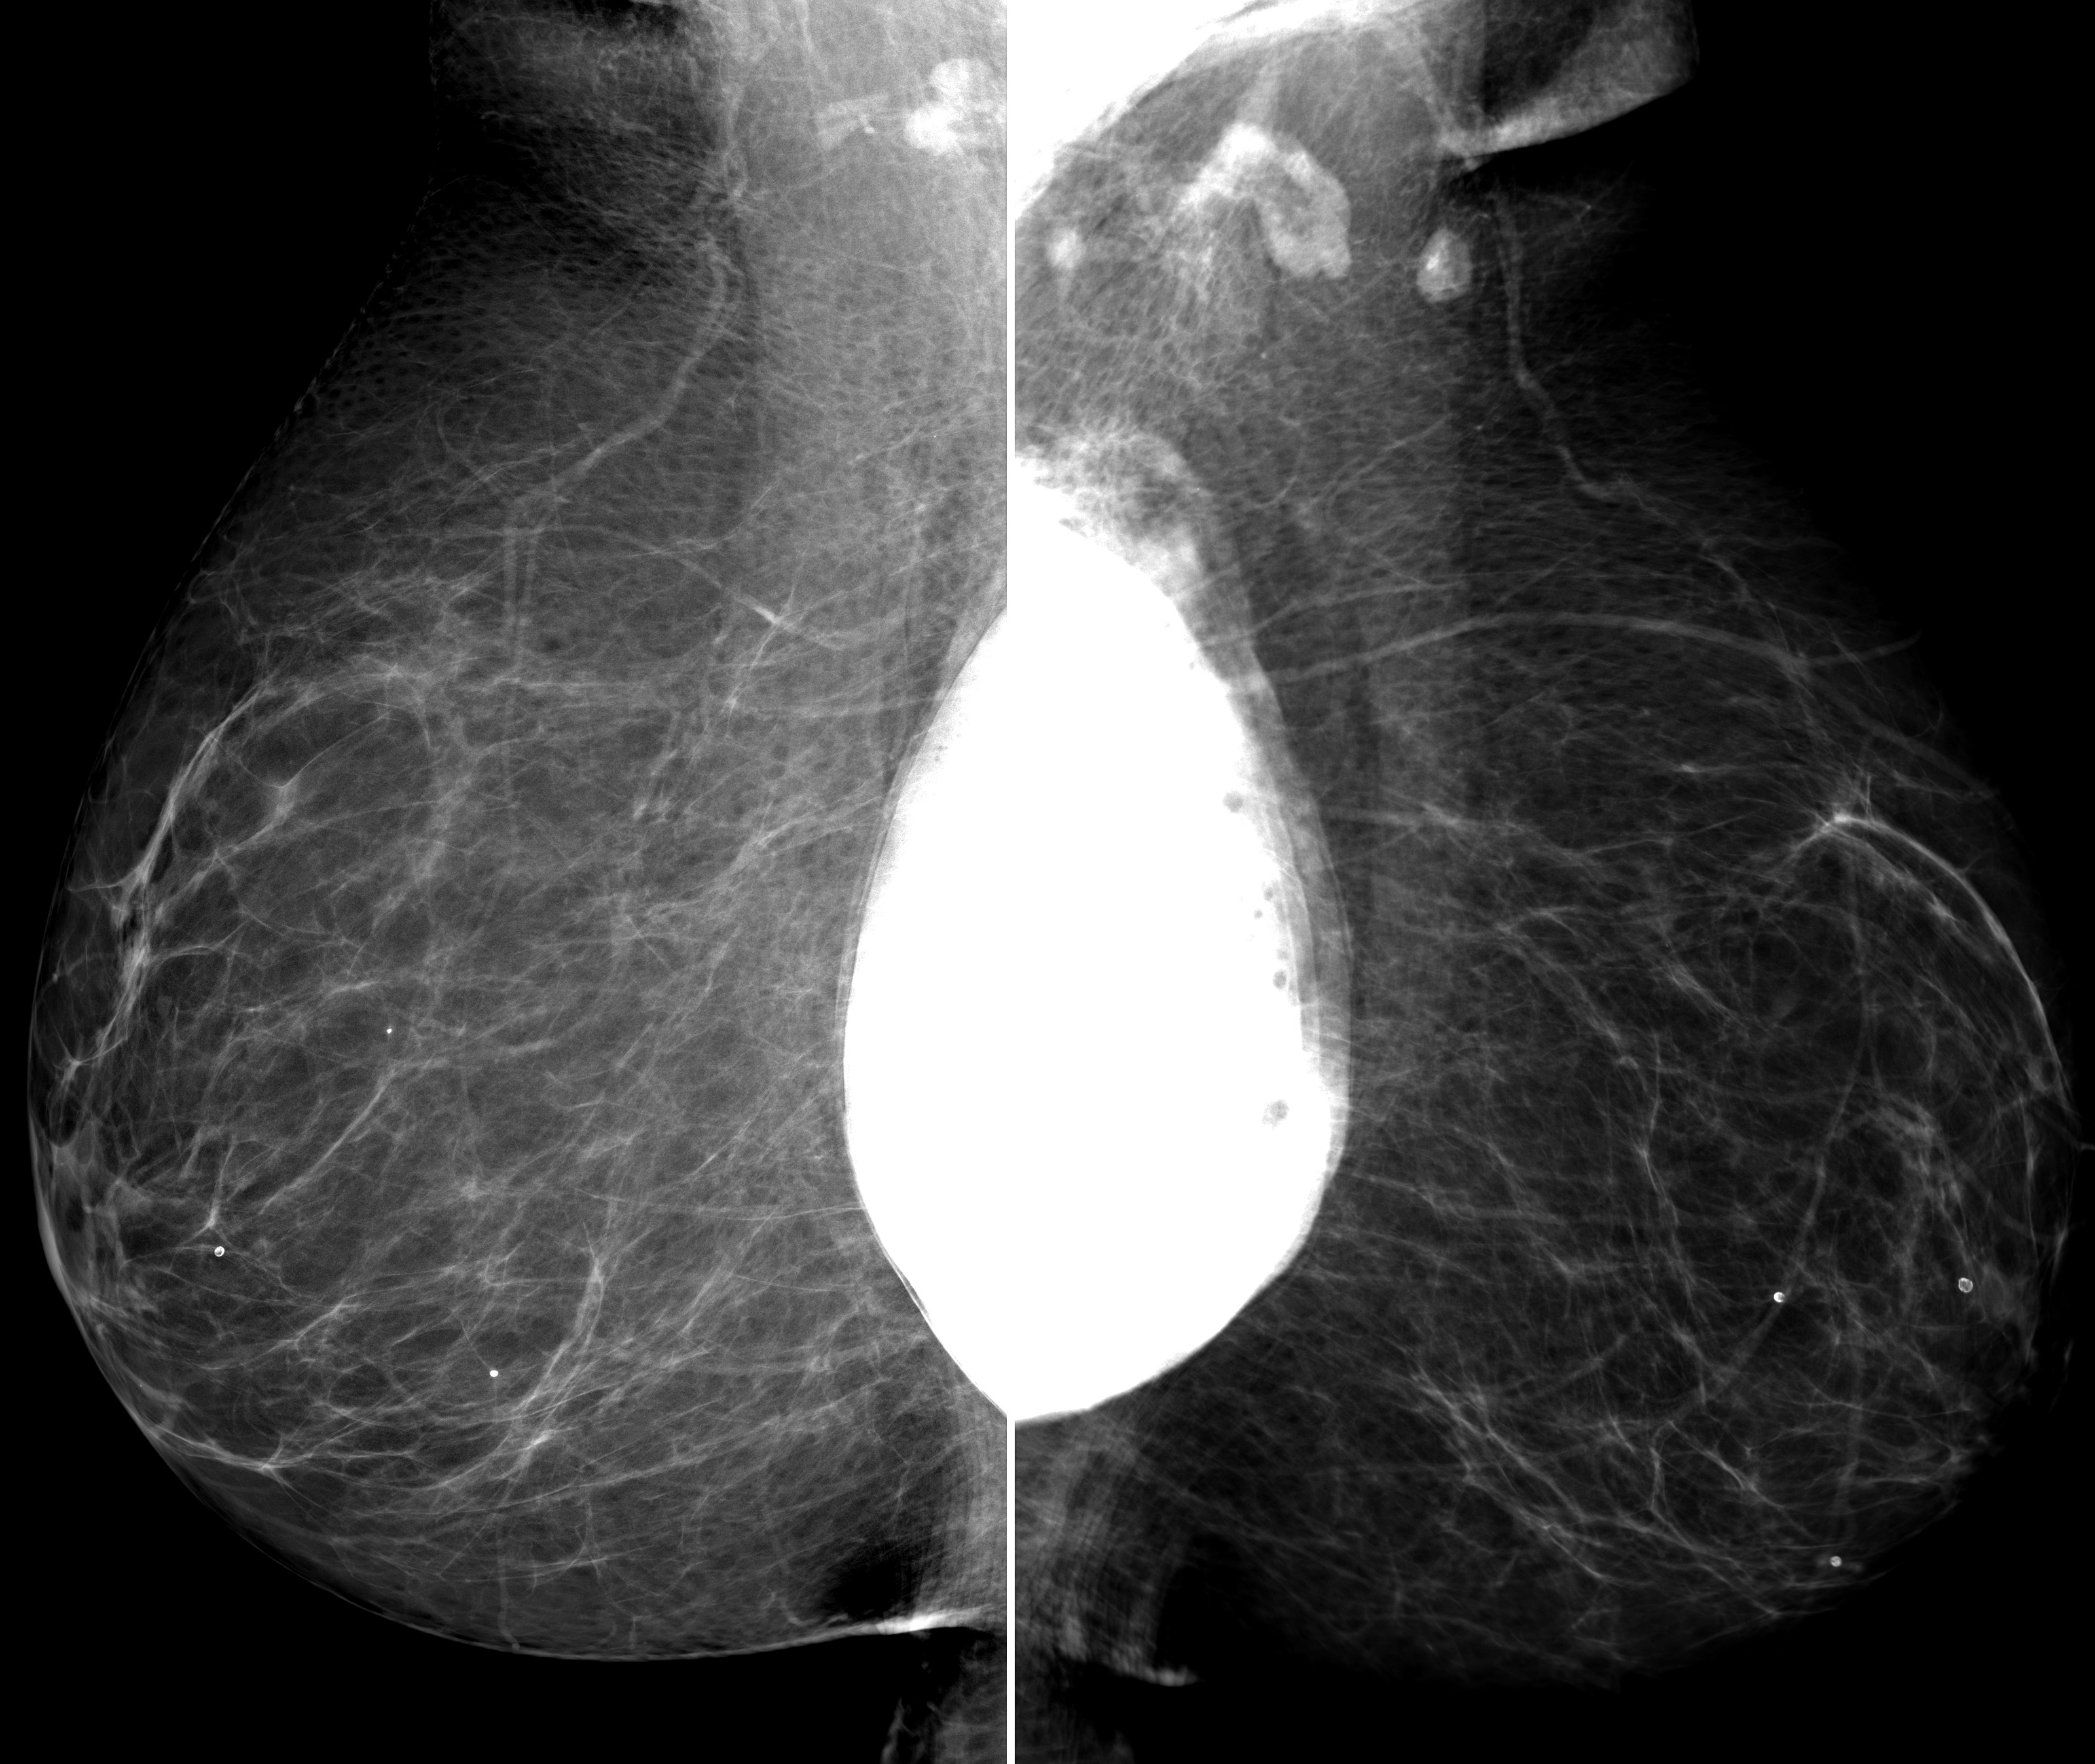

◂Breast Anatomy